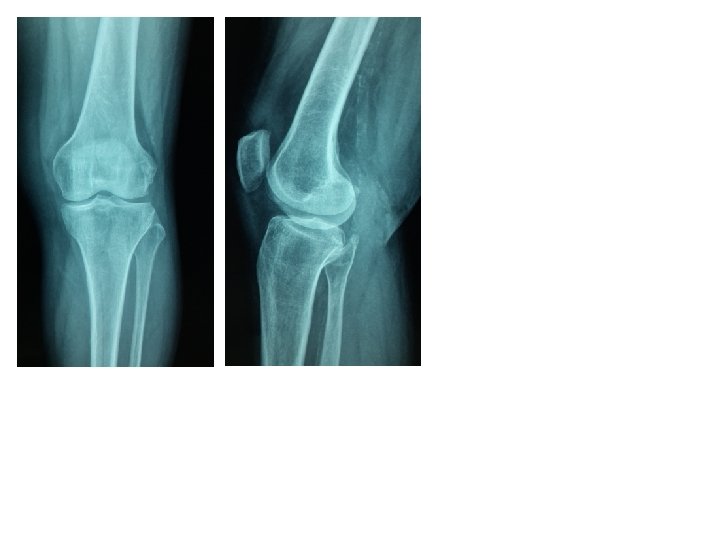

RADIOLOGIE • pose le diagnostic • permet la classification • recherche les lésions associées Rx du genou Face, profil Fracture comminutive

L’incidence fémoro-patellaire difficile à réaliser du fait des douleurs permet de voir les fractures sagittales

Fracture transversale